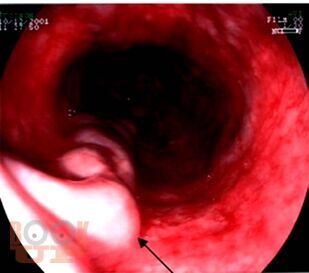

Учебное пособие содержит материал, отражающий современные данные о лечебно-диагностических концепциях основных аномалий развития и приобретённых хирургических заболеваниях детского возраста. В пособии раскрыты ключевые позиции, этиологии, патогенеза, классификации, клинических проявлений, диагностики, консервативного и хирургического лечения, возможных осложнений и исходов хирургических заболеваний у детей. Сделан акцент на эмбриопатогенез и пренатальную диагностику врождённых аномалий развития у детей. Пособие содержит перечень вопросов для самоконтроля, тестовые задания и ситуационные задачи.